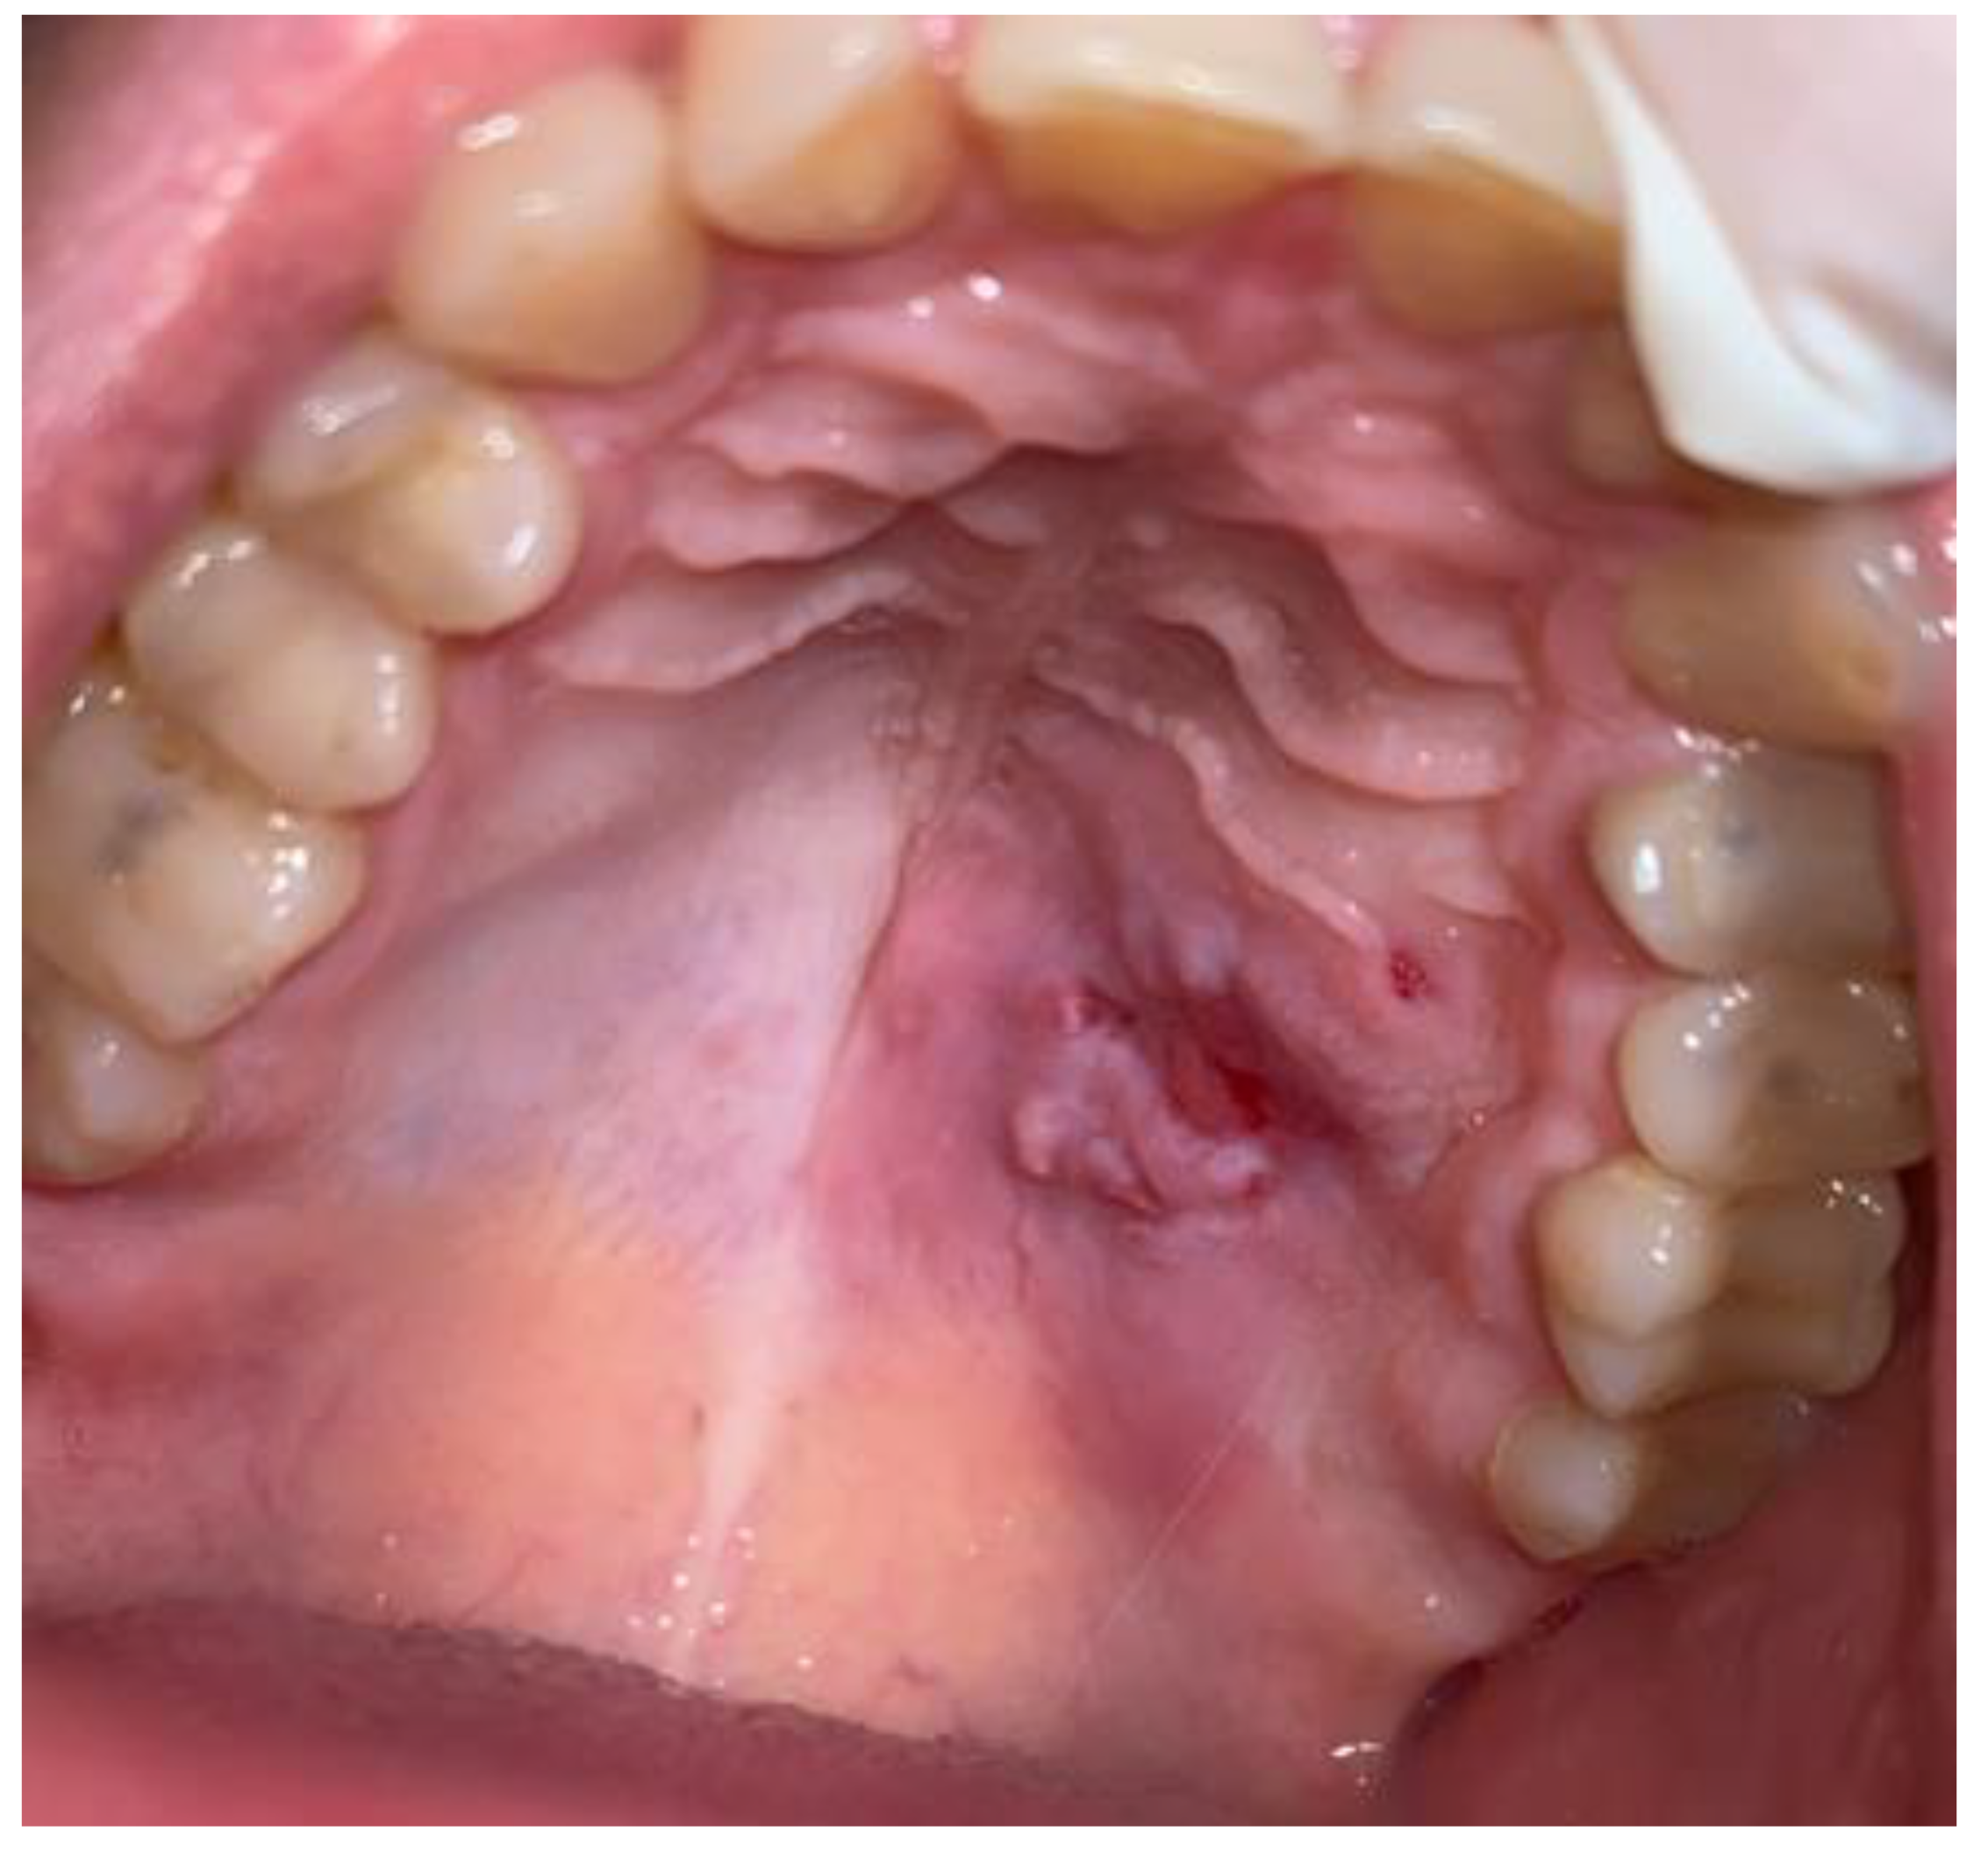

2. Case Description